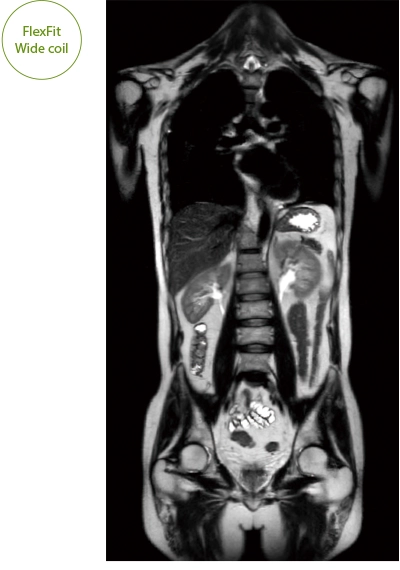

"DLR" is applicable to all body parts and promotes high speed imaging and diagnostic efficiency

IP-RAPID x DLR Plus can also shorten imaging time, allowing more images to be taken in the same examination time.

Additional imaging, such as different image types and cross sections, can be added to the conventional examination to increase the amount of information and make the diagnosis more reliable.

IP-RAPID x DLR Plus can be used for basic imaging such as VolumeScan, RadialScan, HalfScan, and many other imaging methods such as MultiContrastScan FatSep and DWI.

It can also be used with time-consuming scans such as Whole Body DWI and Whole Spine imaging, providing more detailed information in many areas than previously possible.